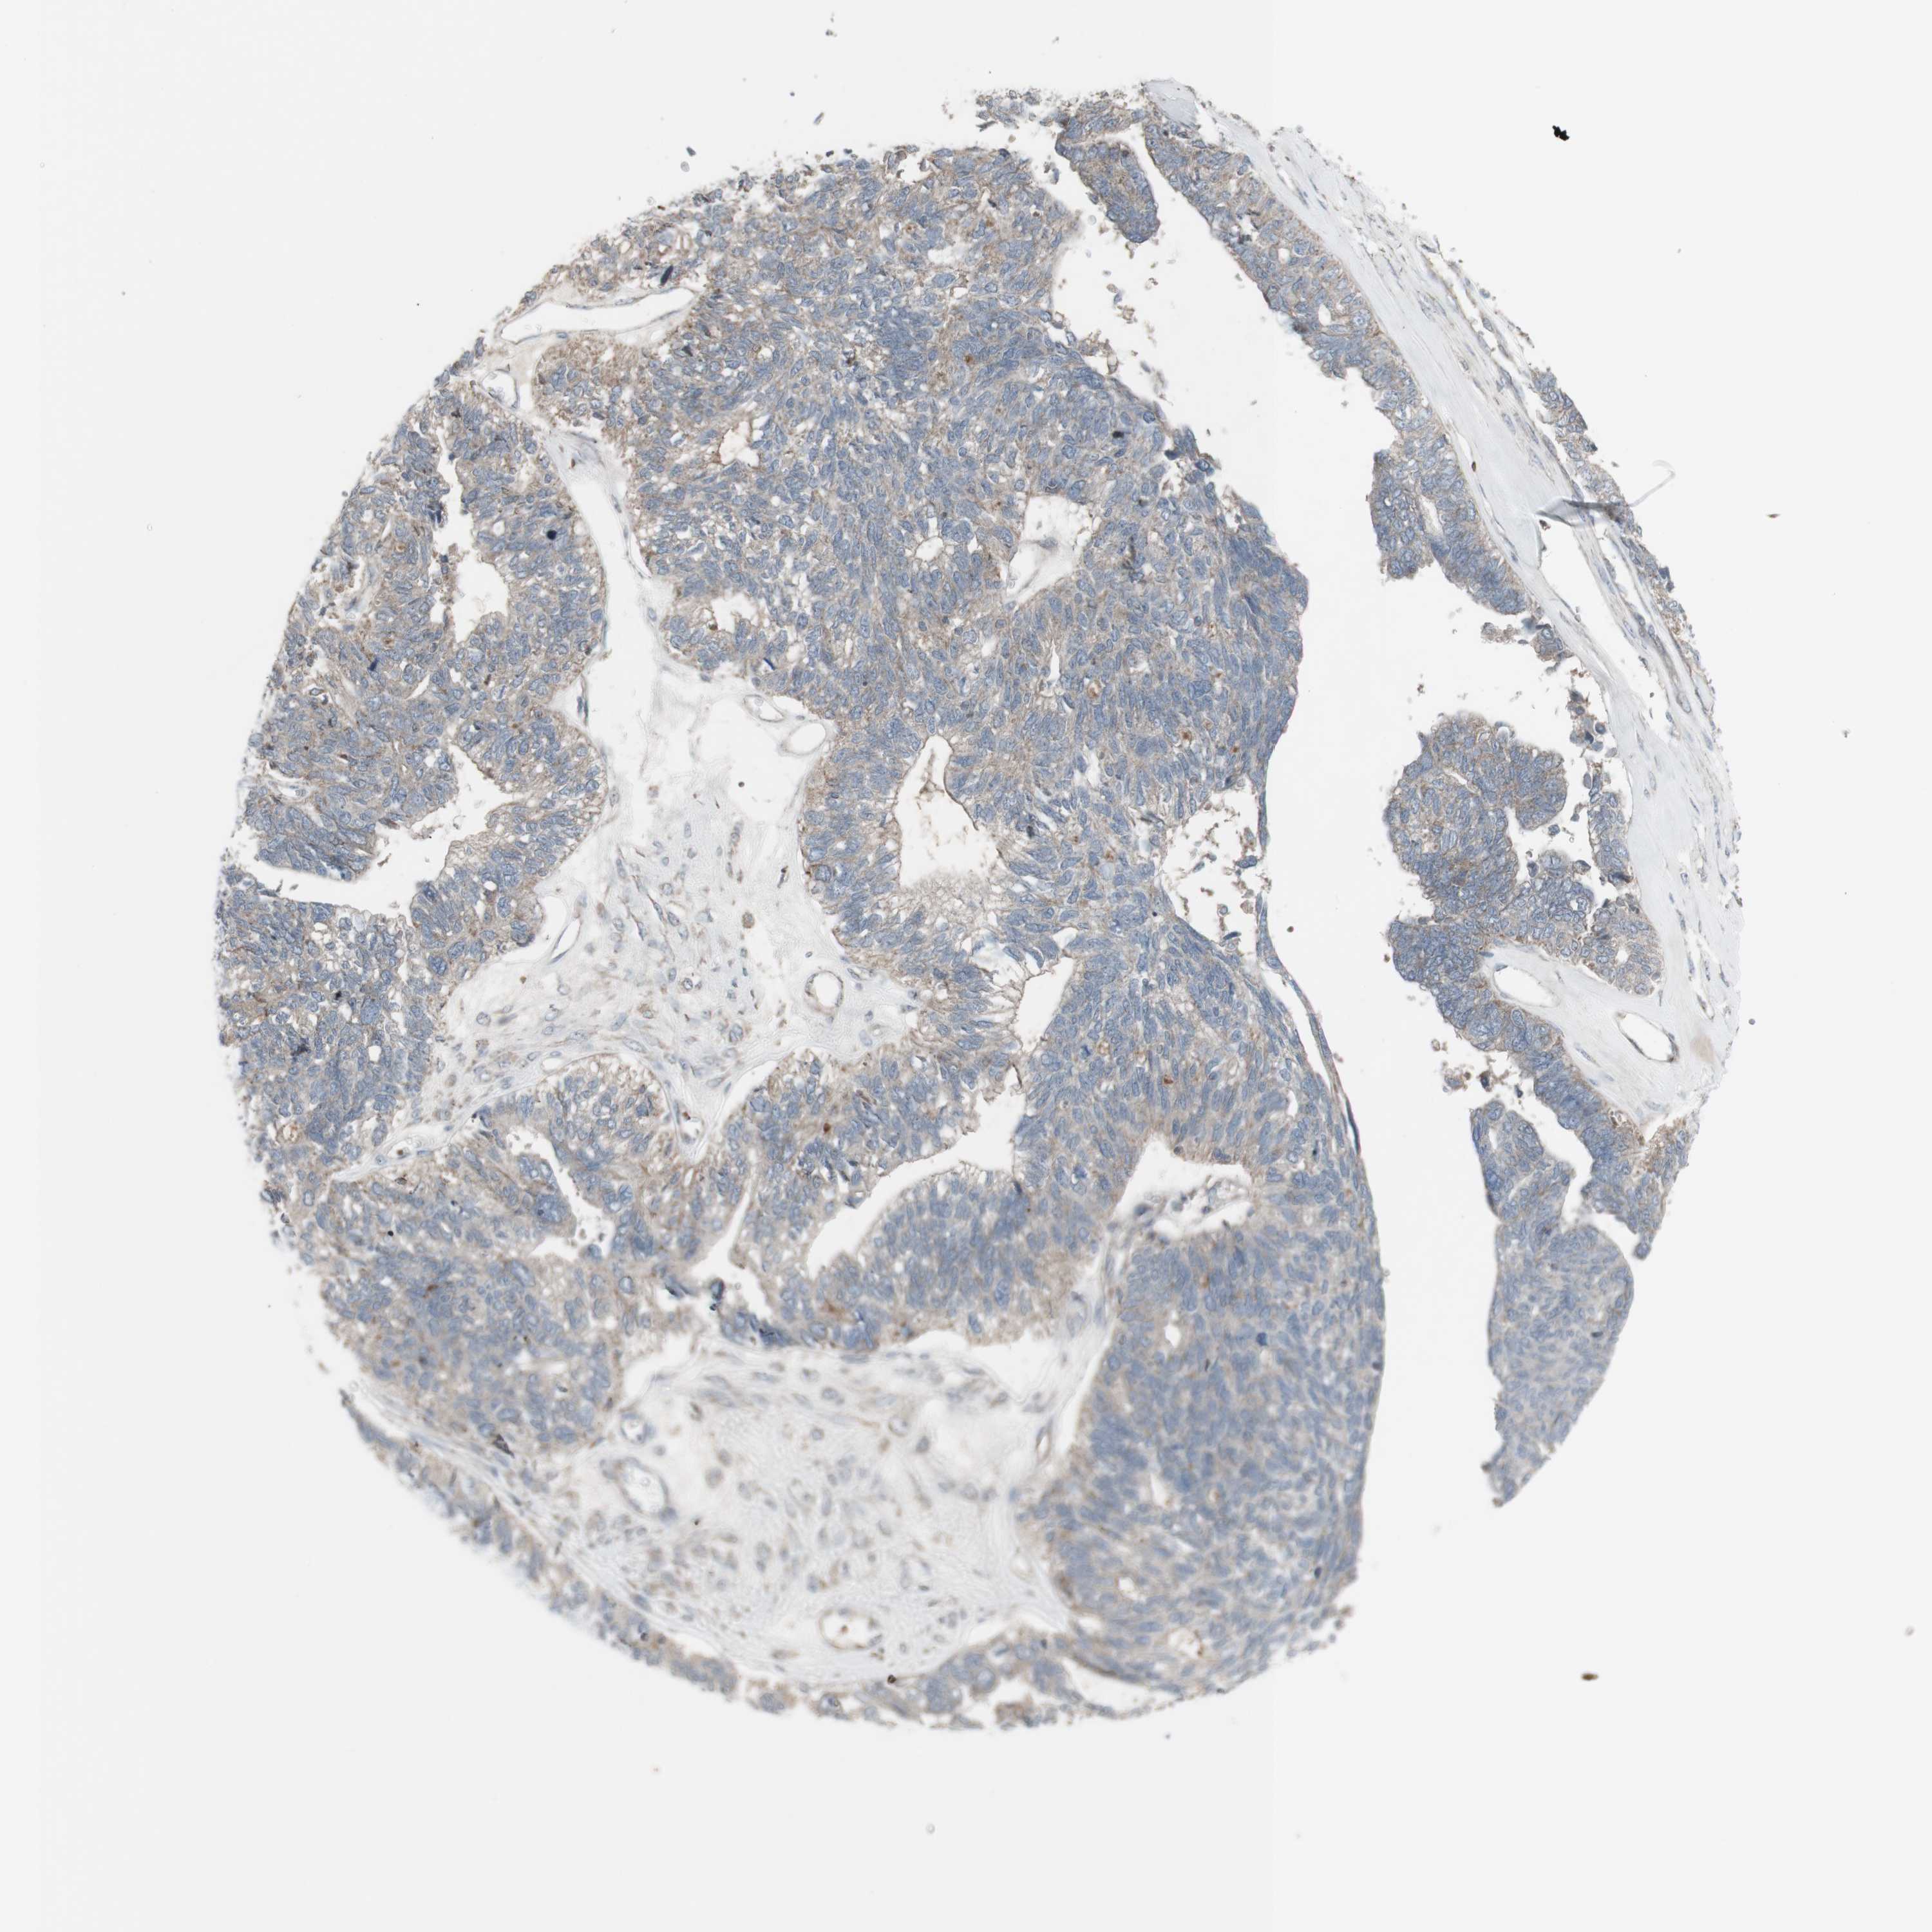

OVARIAN CANCER - Protein expressioni

A mouse-over function shows sample information and annotation data. Click on an image to view it in a full screen mode. Samples can be filtered based on level of antibody staining by selecting one or several of the following categories: high, medium, low and not detected. The assay and annotation is described here.

Note that samples used for immunohistochemistry by the Human Protein Atlas do not correspond to samples in the TCGA dataset.

Antibody stainingi

Antibody staining in the annotated cell types in the current human tissue is reported as not detected, low, medium, or high, based on conventional immunohistochemistry profiling in selected tissues. This score is based on the combination of the staining intensity and fraction of stained cells.

Each image is clickable and will lead to virtual microscopy that enables deeper exploration of all samples and also displays staining intensity scores, fraction scores and subcellular localization as well as patient and tissue information for each sample.

Antibody HPA001844

Cystadenocarcinoma, serous, NOS